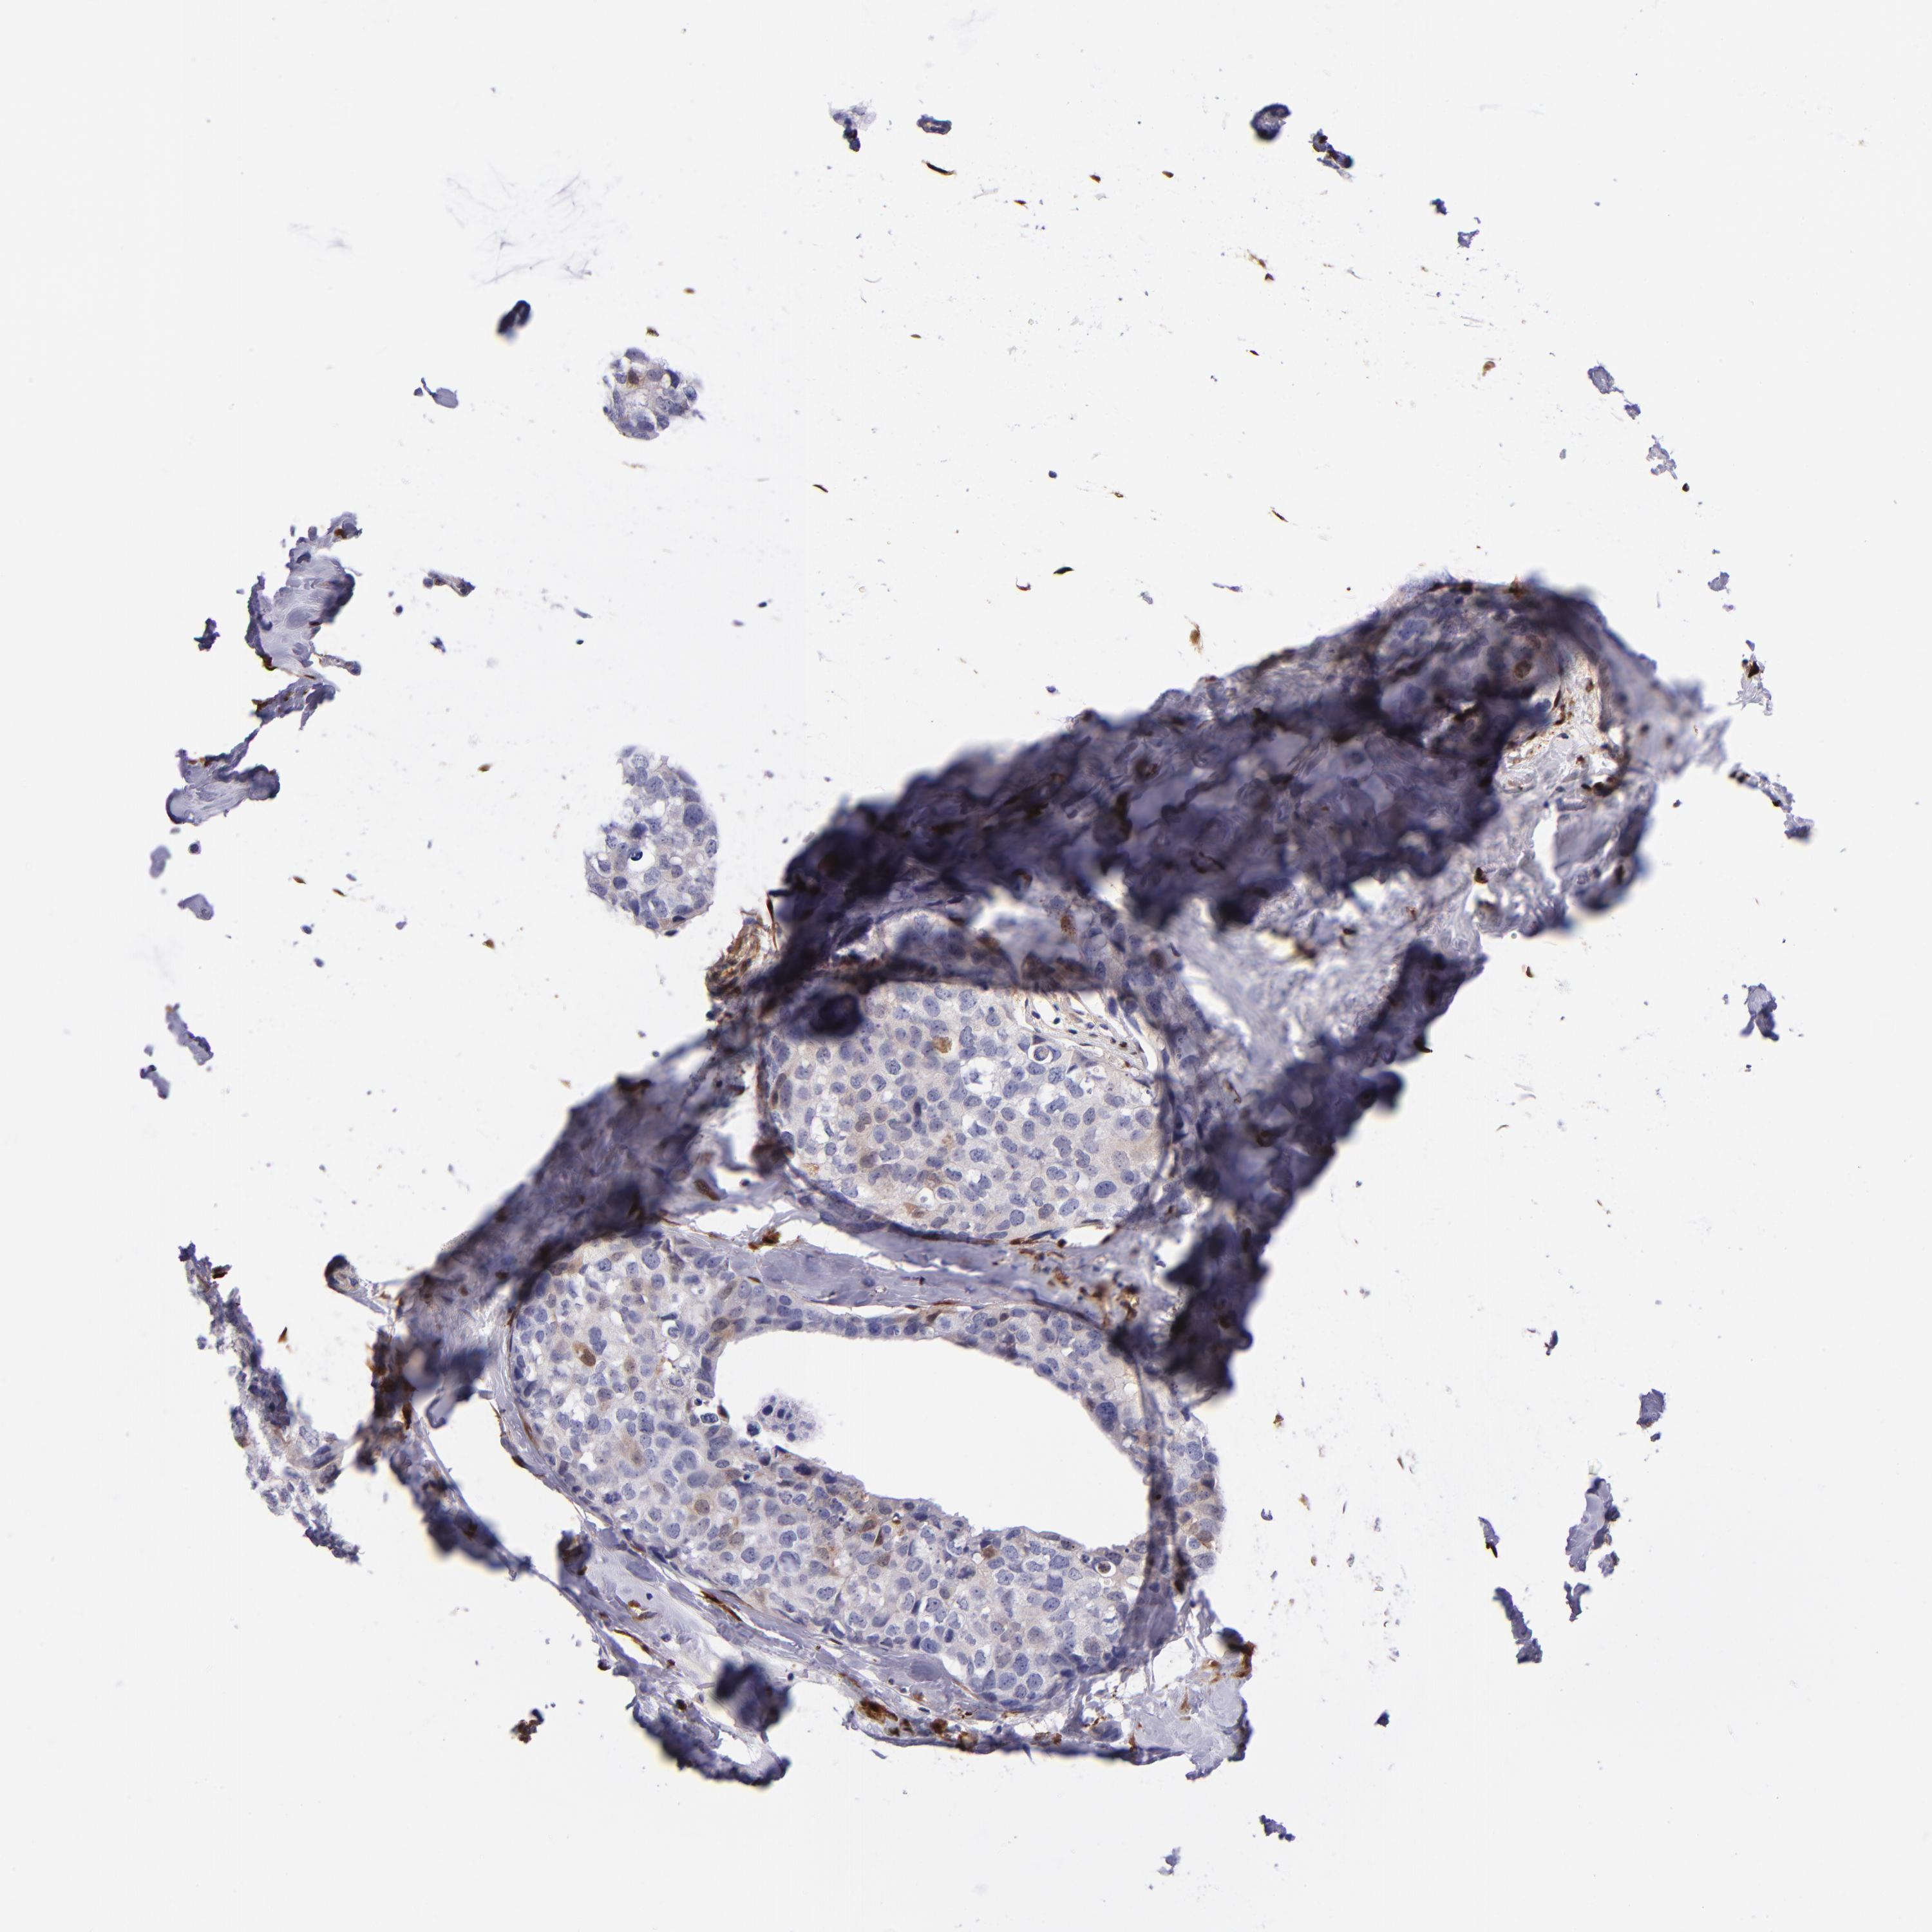

BRCA TCGA BRCA VALIDATION PROTEIN EXPRESSION

ANTIBODIES

AND

VALIDATION